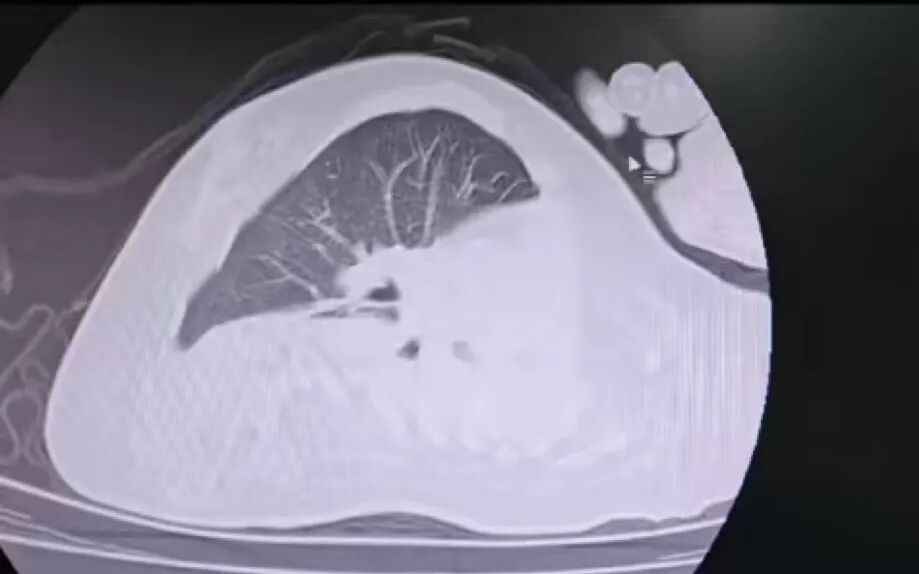

荆楚网(湖北日报)(来信:陈芳芳、李雷)近日,孝感市中心医院儿科团队凭借精湛的技术,成功为一名患有支气管肺炎、脊髓性肌萎缩症(SMA)、脊柱侧弯的特殊儿童进行了纤维支气管肺泡灌洗。术后患者的气道阻塞情况明显改善,目前正处于进一步康复阶段。

孩子因脊髓性肌萎缩症长期卧床不起。他的呼吸肌严重衰弱。他的自主呼吸微弱,几乎丧失了咳嗽、咳痰的能力。此时患支气管肺炎后,肺部感染迅速恶化,命悬一线。更令人不安的是严重的脊柱侧凸,它会导致儿童胸部畸形和气道显着的解剖位移。传统的纤维支气管镜进入路径完全无效。扭曲而狭窄的气道是l就像一个纵横交错的“迷宫”。每一次操作都必须精确到毫米级。

姿势成为另一个“障碍”。既要满足纤维支气管镜的手术要求,又要防止侧弯脊柱受压,防止肌肉萎缩造成关节脱位。每个角度都必须重复测量。同时,还要应对层层术中危机:由于孩子呼吸肌功能几乎丧失,纤维纤维覆盖气道狭窄空间,缺氧、二氧化碳潴留、急性呼吸衰竭、心脏骤停的风险增加;如果灌洗过程中残留液体,肺部感染严重,孩子免疫力低下,导致败血症的风险显着增加。

治疗前

治疗后

为了应对重重危机,孩子们团队制定了详细的行动计划。手术当天,儿科团队在高清内窥镜视野下小心翼翼地操纵器械,避免气道结构扭曲,准确到达伤口,轻柔地完成灌洗、抽吸等一系列操作。

经过团队的不懈努力,手术终于顺利完成。手术后,孩子生命体征稳定,气道阻塞明显改善,目前正在康复中。